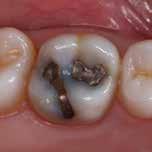

Deep amalgam staining presents one of the most difficult restoration situations to clinicians. In this case only the Transcend composite Universal Body shade was used to replace the amalgam no blocker needed. Note the excellent color blending of the preserved oblique ridge.

Figs. 2a and b: Use of the intraoral camera to check failing fillings. During the consultation, the visualisation of the situation in the patient’s mouth makes the detailed technical explanations much more tangible for the patient and helps provide motivation for the further treatment required.